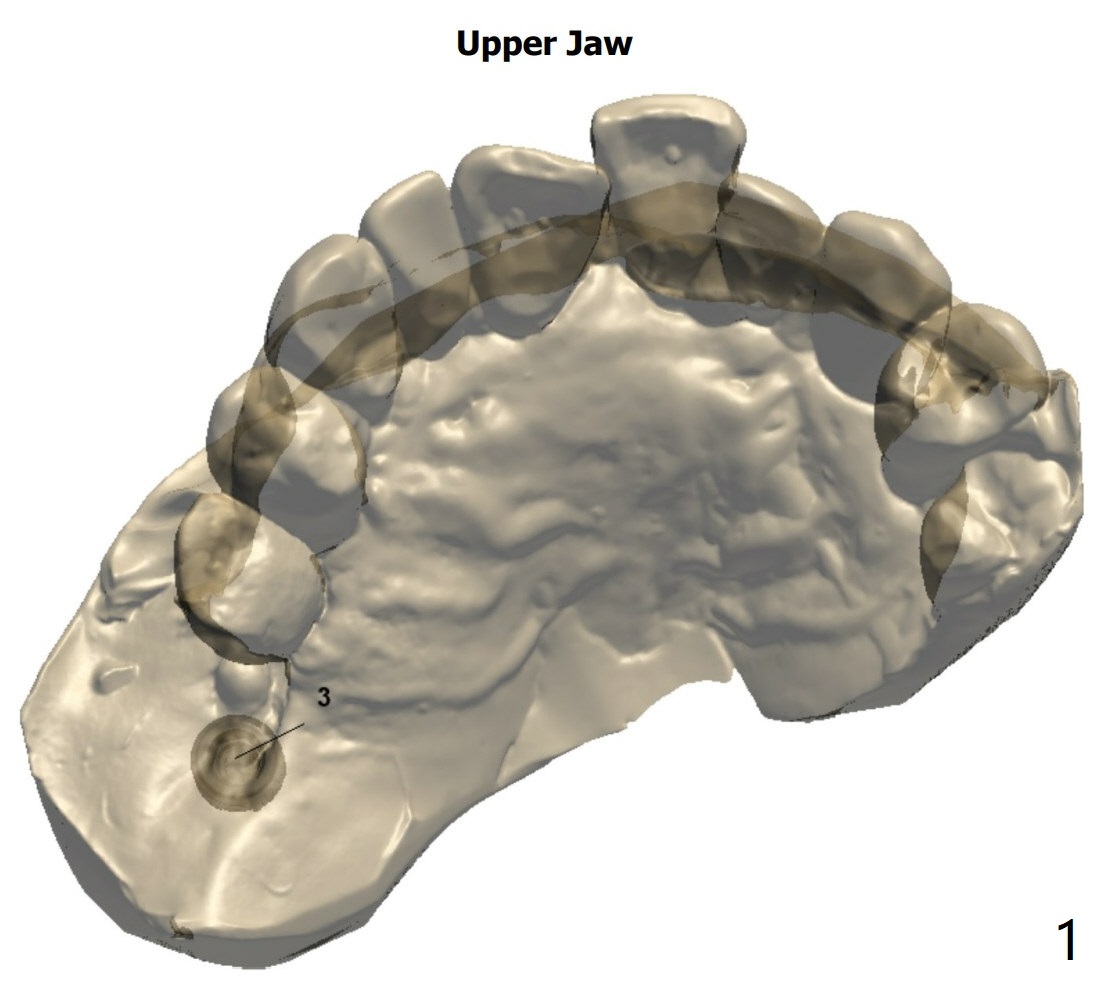

2nd Placement

Post implant removal and bone graft, the sinus floor must be soft and easily penetrated. Use Magic Sinus Lifter and sticky bone.